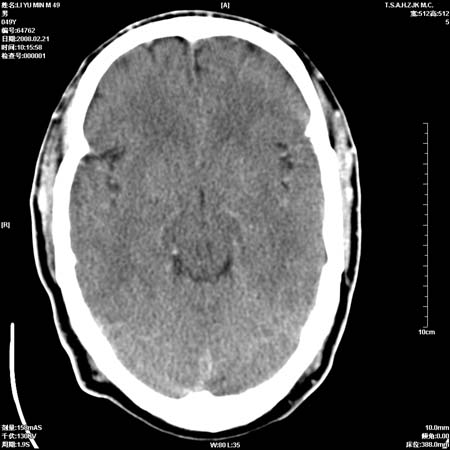

一周后复查ct:

可能为正常。间隔一周蛛血应基本吸收;再过一周复还是这样应该可以肯定了。

一周时间密度未见改变,考虑为正常图像(脑动脉硬化?)。